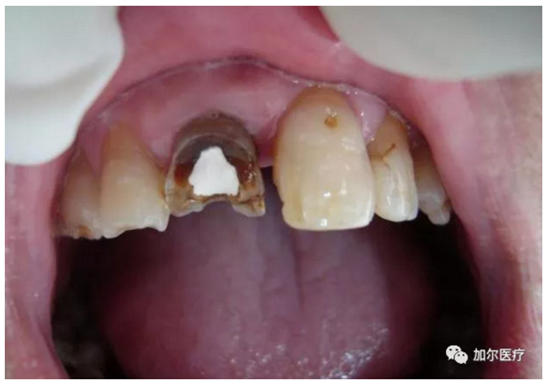

2.png

判斷牙齦上是否起膿包!

1、很遺憾地告訴你,一旦長膿包說明牙髓失去活力,甚至病變牙髓沉積在根尖部位刺激根尖周圍組織,瘺管受感染起炎癥后膿液流出,穿透牙槽骨起膿包,這種病髓就得抽出,清洗消毒髓腔以及根尖部位,并且還得封消炎藥。

2、其實說的就是根管治療,只不過多了清理根尖部位,還有牙齦膿包位置的消炎殺菌,有些患者深度蛀牙引起牙痛,明明可以早點做根管治療,拖到病髓壞死發(fā)生根尖周炎,這時候再來治療還得加錢治根尖炎,結(jié)果反而更糟還要花更多錢!